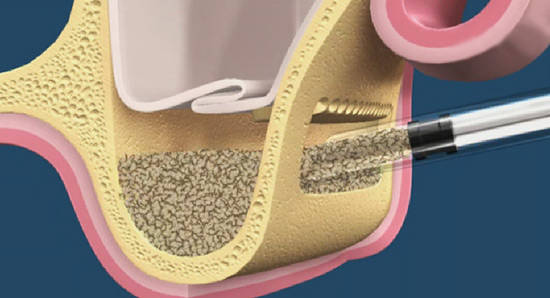

Есть простое правило по выбору места доступа в субантральное пространство. Чем ниже его делаешь — тем проще получается операция синуслифтинга. Ну и, нижнюю границу верхнечелюстной пазухи определить очень просто — она просвечивает.

Создание доступа в субантральное пространство:

Получившуюся «крышечку» можно использовать как для закрытия возможных перфораций, так и для отделения субантрального пространтства от внешней среды. Вместо барьерной мембраны.

Ну вот, в данном случае мы используем эту «крышечку» для отделения зоны синуслифтинга от верхнечелюстной пазухи. У пациентки очень тонкая. почти прозрачная слизистая оболочка гайморовой пазухи, для перестраховки ее лучше прикрыть либо костным фрагментом, либо барьерной мембраной (типа Geistlich BioGide или Bottis Jason). Не рекомендую использовать дешевые мембраны типа «Пародонкол» или корейско-израильских производителей. Они малоэлластичные, имеют острые края — ими очень легко повредить тонкую и нежную оболочку гайморовой пазухи — если и не было перфорации, то Вы ее, стопудово, получите.

Теперь смело готовим лунку под имплантат. Правило такое — сначала лунка, потом спейсер (в данном случае Bioss+аутокостная стружка). Если делать наоборот, что за счет ирригации, вы, скорее всего, размоете весь материал при подготовке лунки.

Теперь заполняем субантральную полость остеопластическим материалом. Я использую Bioss:

Остеопластический материал — всего лишь спейсер (от слова SPACE — пространство). Он НЕ ПРЕВРАЩАЕТСЯ В КОСТНУЮ ТКАНЬ, не регенерирует и не ускоряет регенерацию костной ткани. Какой бы марки этот материал ни был. Теоретически, можно взять простой песок, обработать его должным образом — и использовать как остеопластический материал.

Задача любого спейсера — создать и удержать пространство, необходимое для регенерации костной ткани. Регенерируют клетки костной ткани, малодифференцированные клетки крови, а не материал. Но, чтобы нормально регенерировать в нормальную кость, им нужно пространство. И время. Как минимум, 3 месяца.

Нельзя заталкивать много материала. На одну верхнечелюстную пазуху у меня уходит, в среднем, меньше 0.5 грамма Bioss, либо 0.5 куб. см, если говорить об объеме. Материал не должен слеживаться — поэтому я выбираю крупные фракции.